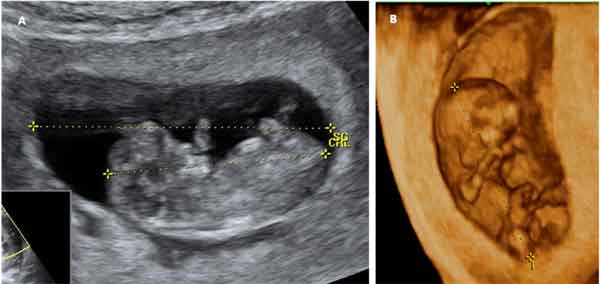

A partir de aquí, la semana 10 de gestación, el embrión ya tiene forma humana. Termina, pues, el periodo embrionario y empieza el periodo fetal. Tu bebé mide unos 32 milímetros desde la cabeza a la rabadilla al comienzo de la semana, y pesa aproximadamente 2 gramos. Al final de la semana 10 de embarazo, se han formado prácticamente la totalidad de órganos y sistemas del pequeño.